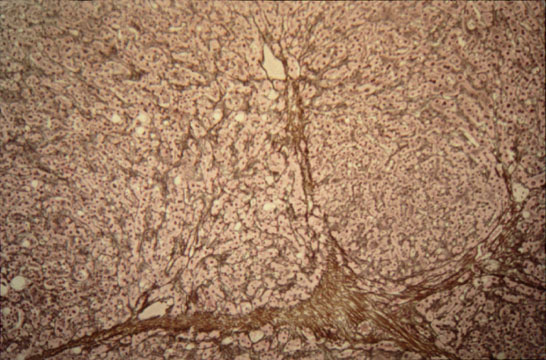

Advanced cirrhosis

Fig.85 - ADVANCED CIRRHOSIS: Wide scars containing clusters of regenerative hepatocytes. Large scars may contain large portal fields recognizable with a stain for elastic fibers.